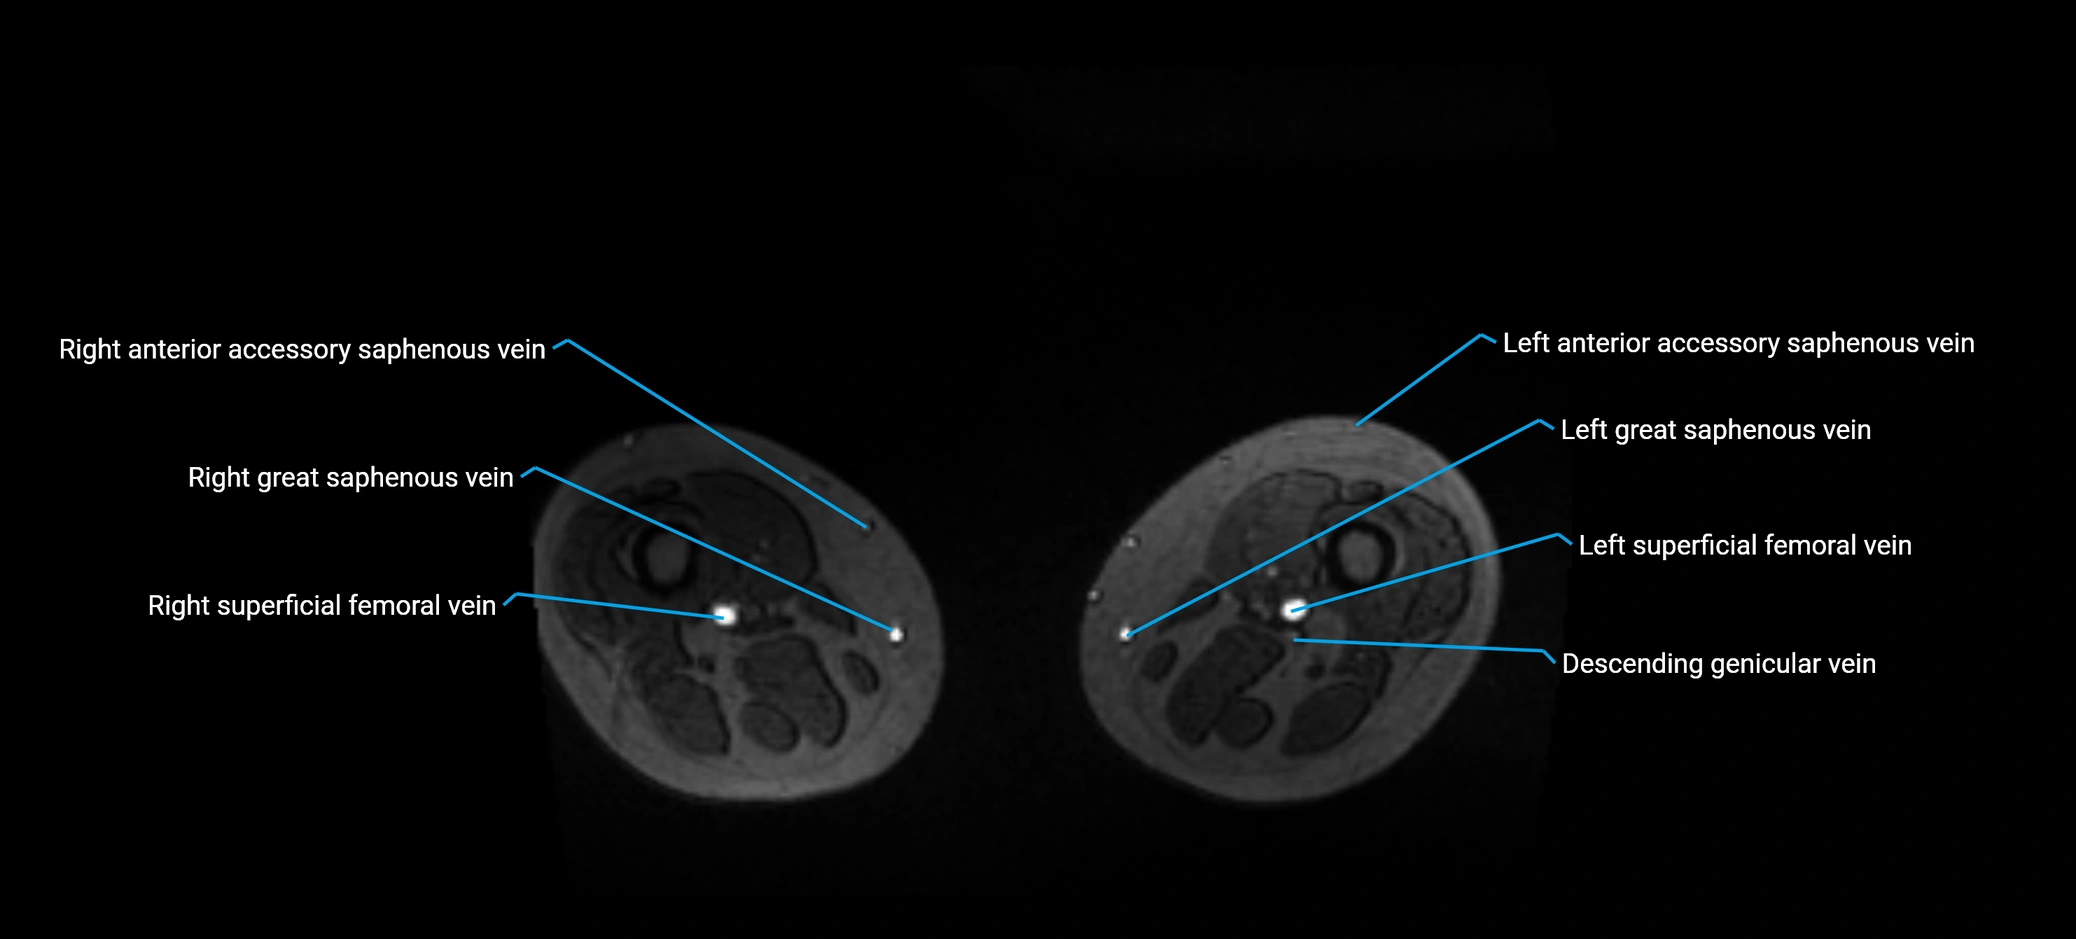

MRV TOF (Time-of-Flight MR Venography):

• Appears as a bright, high-signal vascular channel representing flowing blood

• Clearly shows branching pattern of right portal vein into anterior and posterior branches

• Best in coronal or axial reconstructions for segmental mapping

• No need for contrast, relies on flow-related enhancement